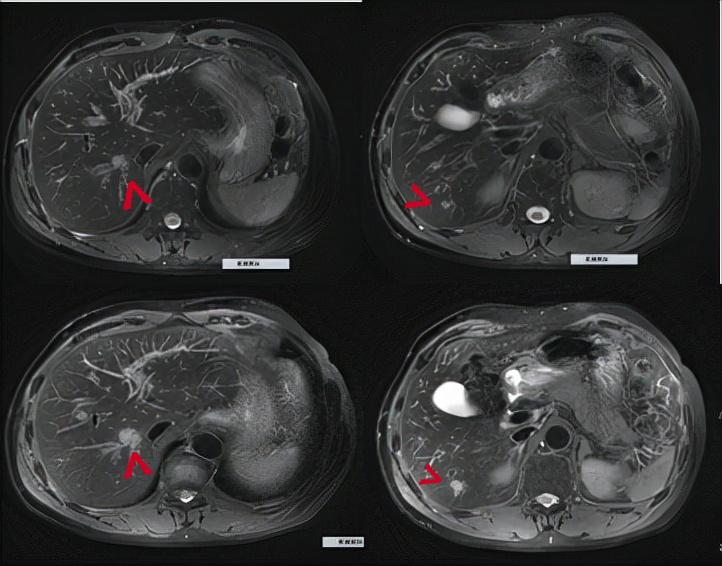

2020年11月复查上腹部MRI示:肝内多发转移灶较前增大,考虑治疗进展。

临床判断:鼻咽癌肝内多发转移免疫治疗后寡进展。

MRI示:肝内病灶较前增大,显示为寡进展。上图:耐药前;下图:耐药后

2020年11月:局部影像引导容积调强放疗,50Gy/20F/4w,替吉奥同步化疗2周期。

疗效评价:大PR。

MRI示:肝内病灶放疗后明显缩小。上图:放疗前;下图:放疗后